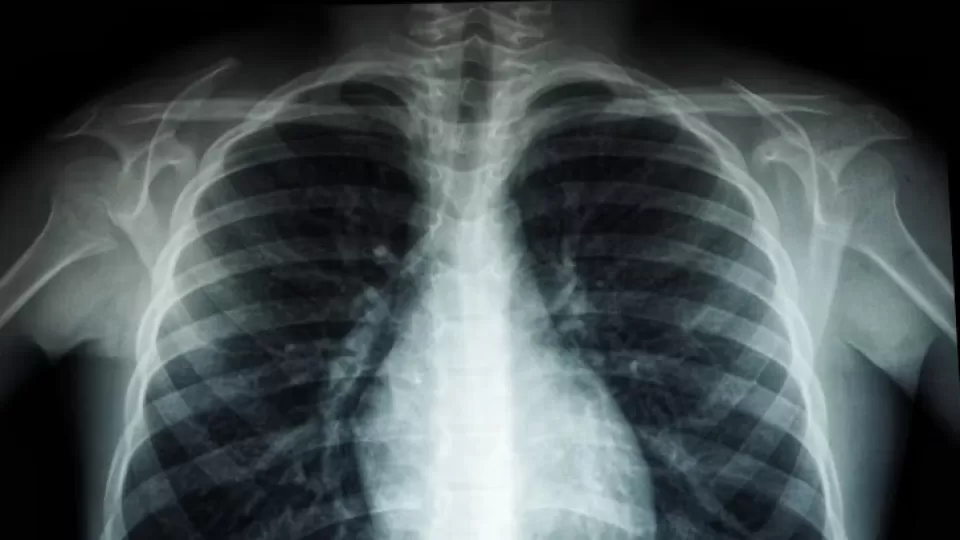

La Secretaría de Salud de México ha emitido una alerta oficial ante un repunte significativo de casos de tosferina (pertussis) proyectado para el año 2025. Esta situación exige una atención prioritaria de la ciudadanía y las instituciones de salud para mitigar la propagación de esta enfermedad respiratoria altamente contagiosa.

Según el comunicado de la dependencia, el incremento esperado en la incidencia de tosferina representa un desafío importante para la salud pública nacional. La tosferina es una infección bacteriana que afecta principalmente las vías respiratorias y es particularmente peligrosa para lactantes y niños pequeños, quienes pueden desarrollar complicaciones graves como neumonía, convulsiones, daño cerebral e incluso la muerte.